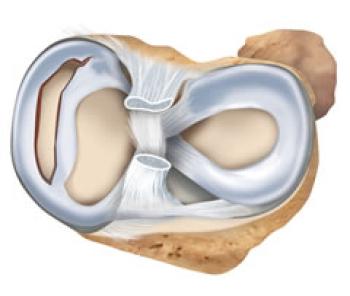

![Menisküs]()

Menisküs

Patella (Diz kapağı) Çıkığı 1646 OkunmaMenisküsler nasıl yırtılır?

Menisküs yırtığı diz ekleminde meydana gelir. Bu yırtık ayak sabitken ani bir dizden dönme hareketi, yüksekten düşme veya dizin üzerine aşırı bir k...